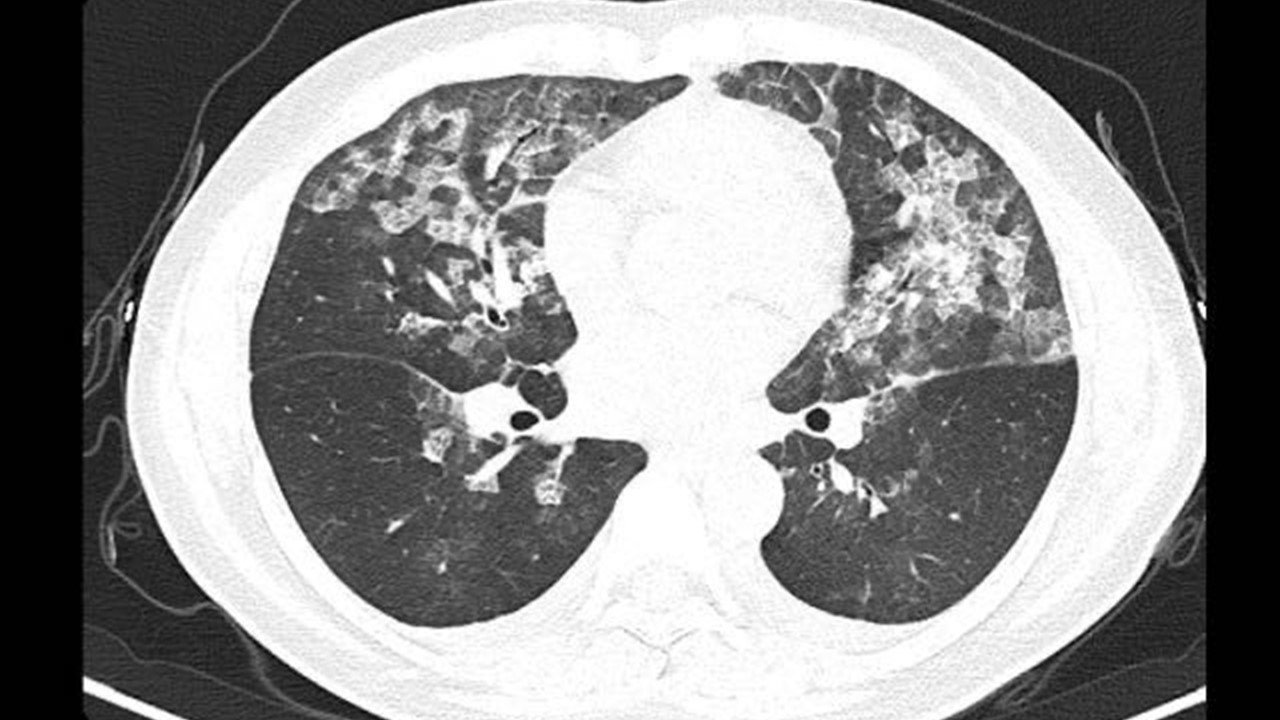

CTスキャンによる検査を行ったところ

患者の「肺に白い影」が見つかったそうです。新型コロナ肺炎の特徴と一致

家じゅうを消毒していたと判明次亜塩素酸ナトリウムを主要成分とするアレルギー性肺胞炎と診断されました。